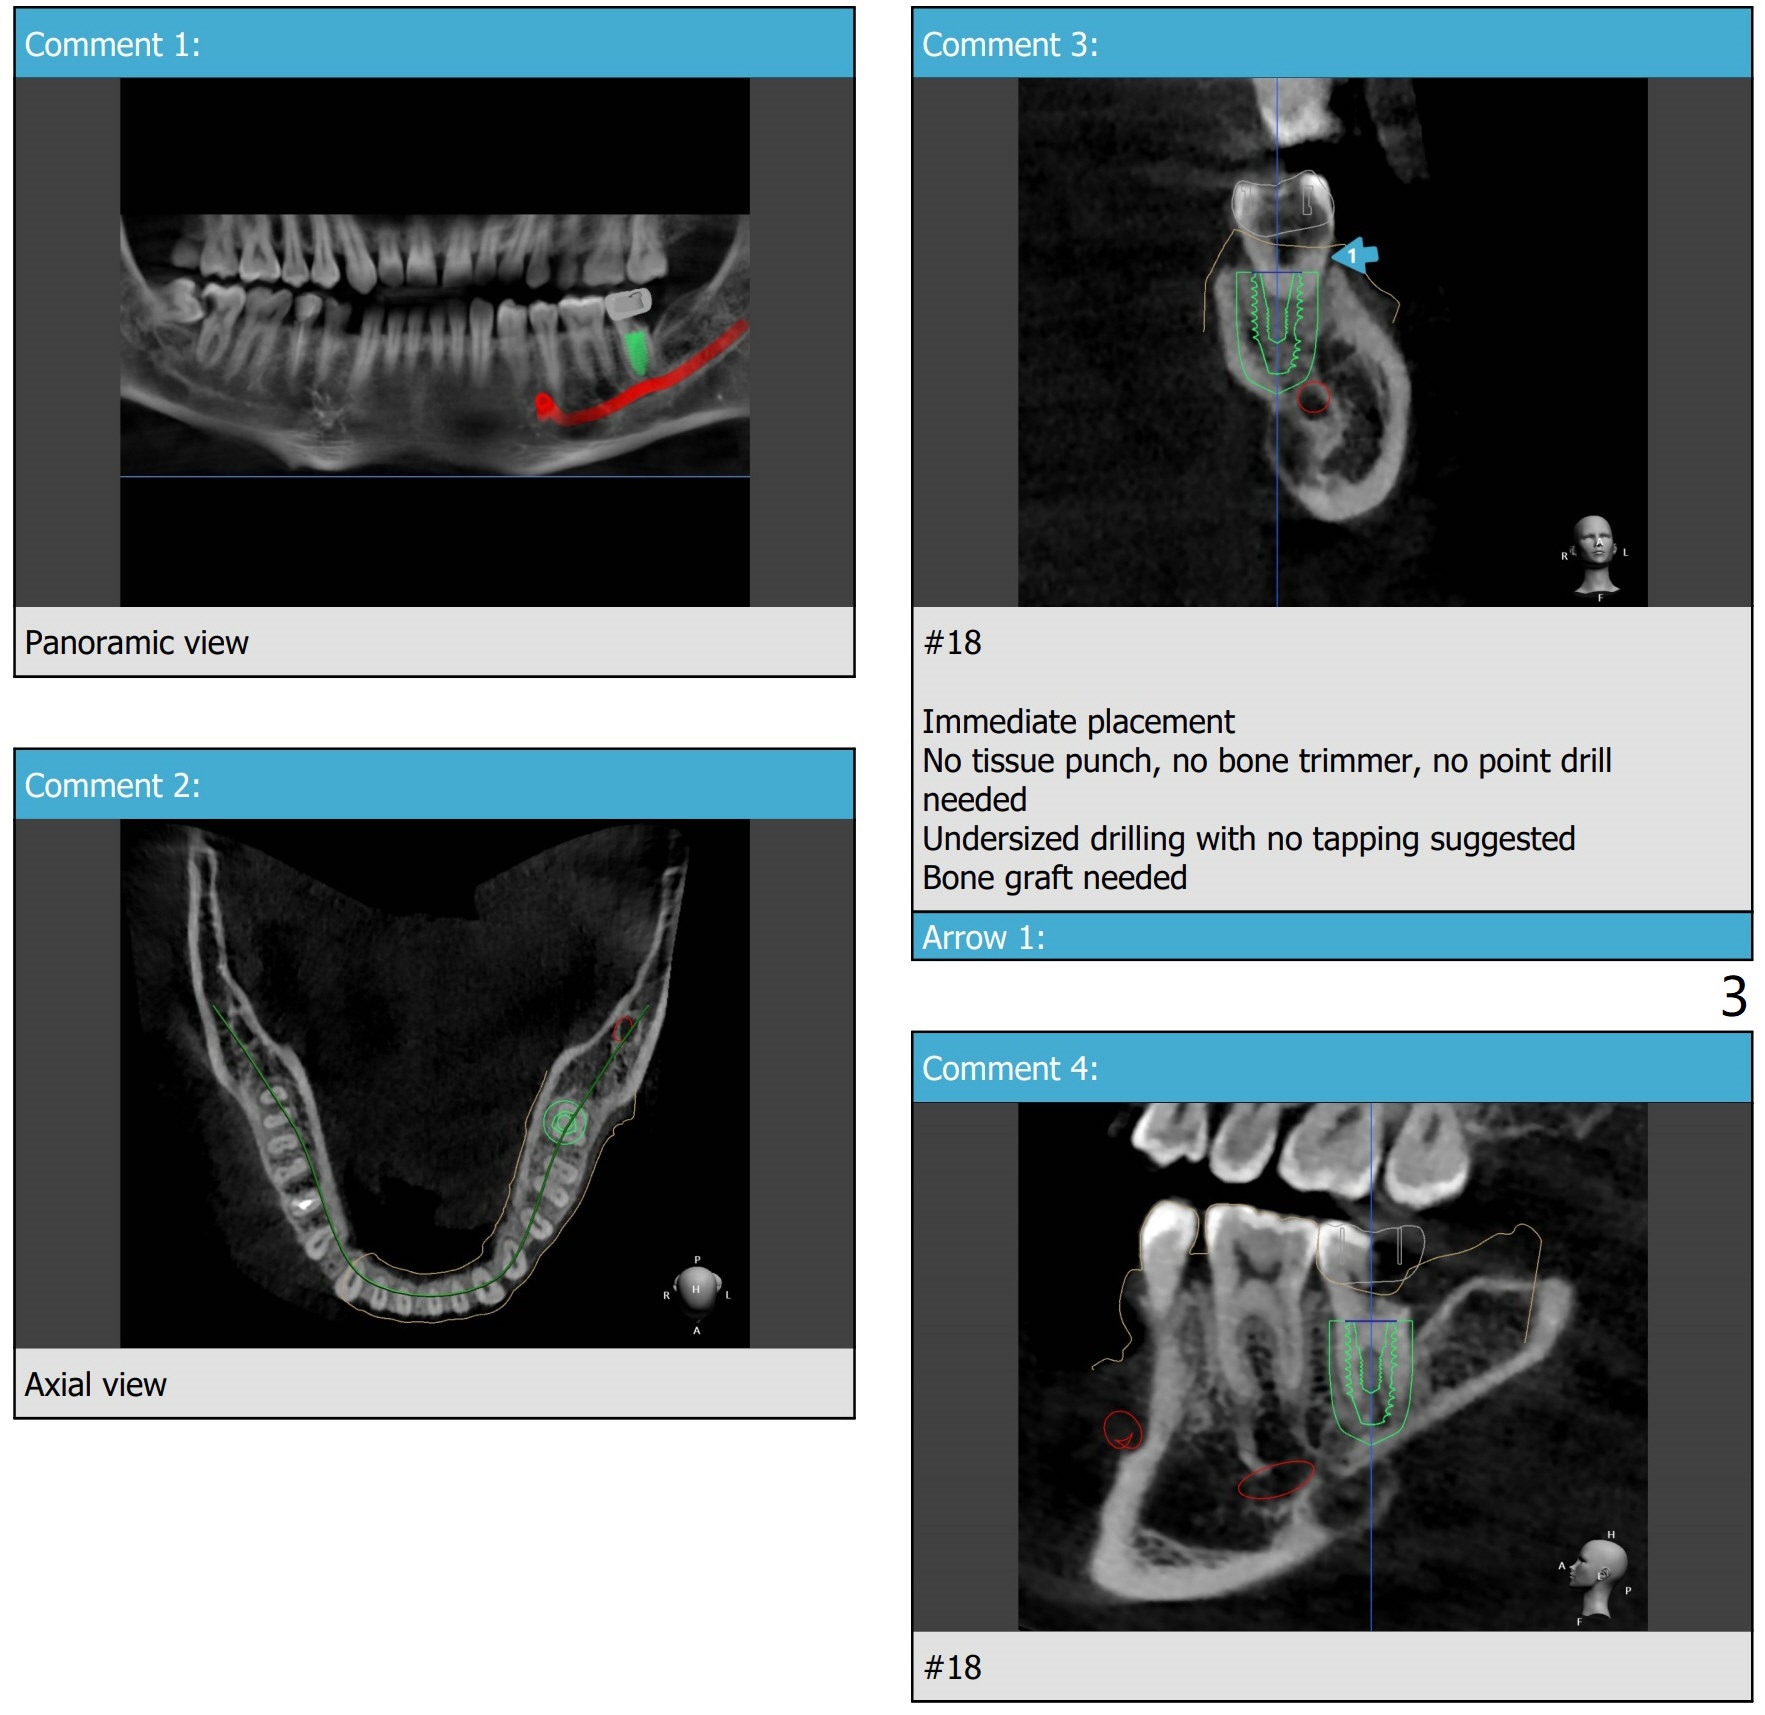

9 mm offset

A 35-year-old man has severe caries #18 D due to 3rd molar impaction. There appears no bone loss at #18. Small amount of sticky bone with PRF membrane should be prepared.